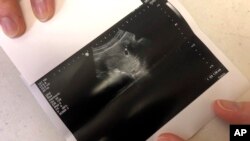

وزارت بهداشت ایران، خبر تولد ۱۲ کودک با سندروم «داون» طی سال گذشته و تنها در یک مرکز آزمایشگاهی را که روزنامه شرق خبر آن را به نقل از رئیس آزمایشگاه تخصصی سلامت جنین منتشر کرده بود، تکذیب کرد.

تست‌های غیرتهاجمی پیش از تولد که با تجزیه و تحلیل خون فرد باردار برای یافتن ناهنجاری‌های کروموزومی شایع‌تر انجام می‌شود، معمولا با دقت بالا و درصد خطای پایین می‌توانند تشخیص دهند که آیا نوزاد در معرض خطر تریزومی ۲۱ ( سندرم داون)، تریزومی ۱۸ (سندرم ادواردز) و تریزومی ۱۳ (سندرم پاتائو) قرار دارد یا خیر. گاهی اوقات هم می‌توان چندین اختلال نادر را نیز در ده هفته نخست بارداری غربالگری کرد.

در صورتی که نتیجه این دسته از آزمایش‌های غربالگری غیرطبیعی باشد، پزشکان معمولاً آزمایش‌های تشخیصی بیشتری را برای تعیین وجود مشکلات احتمالی در نوزاد پیشنهاد می‌کنند.

بسیاری از ناهنجاری‌های ژنتیکی را می‌توان با استفاده از روش‌های غربالگری پیش از تولد تشخیص داد.